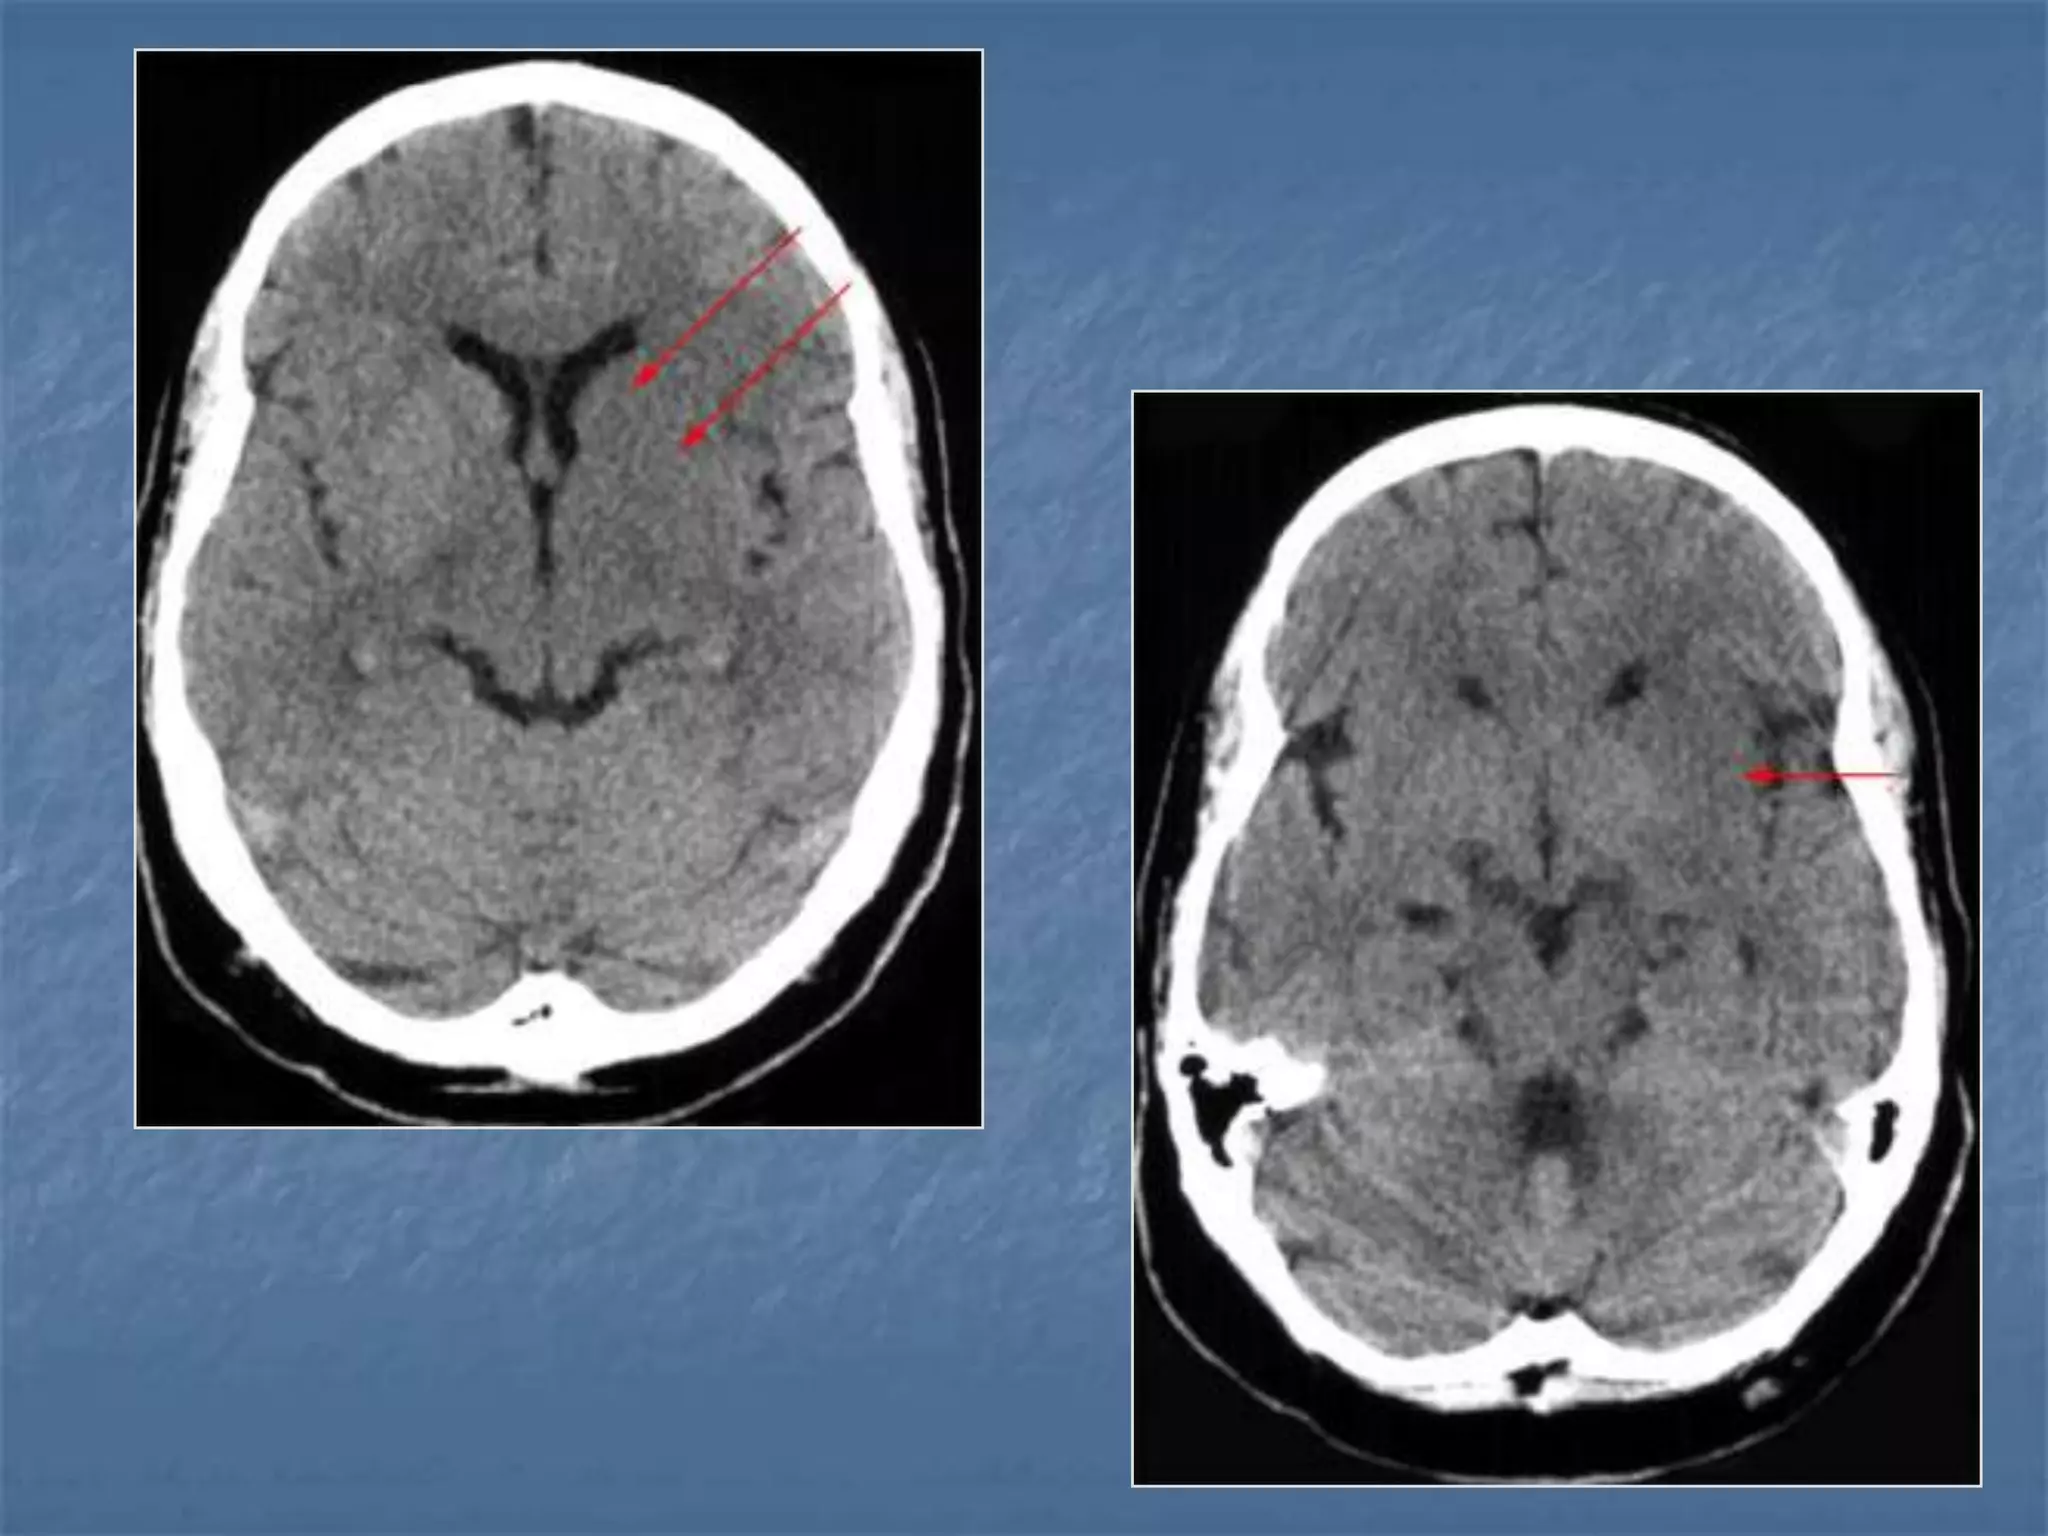

Diffuse Axonal Injury

 Diffuse axonal injury is often referred to as "shear injury". It is the most

common cause of significant morbidity in CNS trauma. Fifty percent of all

primary intra-axial injuries are diffuse axonal injuries. Acceleration,

deceleration and rotational forces cause portions of the brain with

different densities to move relative to each other resulting in the

deformation and tearing of axons. Immediate loss of consciousness is

typical of these injuries. The CT of a patient with diffuse axonal injury may

be normal despite the patient's presentation with a profound neurological

deficit. With CT, diffuse axonal injury may appear as ill-defined areas of

high density or hemorrhage in characteristic locations. The injury occurs in

a sequential pattern of locations based on the severity of the trauma. The

following list of diffuse axonal injury locations is ordered with the most

likely location listed first followed by successively less likely locations:

- Subcortical white matter

- Posterior limb internal capsule

- Corpus callosum

- Dorsolateral midbrain